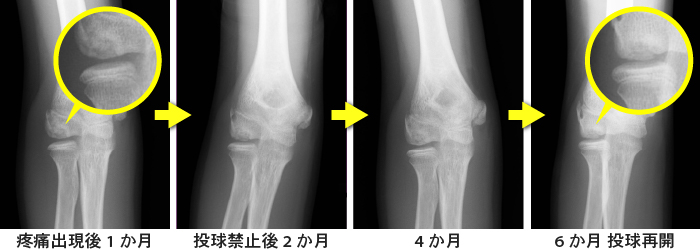

肘の骨軟骨炎は治るまでどのくらいかかりますか?

回復のスケジュールは怪我の程度によって異なります。

OCD関連の骨折の中には軽度ですぐに治るものもありますが、手術が必要で回復までに長い時間がかかるものもあります。

しかし、軽度のOCDであっても、完全に回復するには通常数か月かかります。手術が必要な場合、スポーツやその他の活動に戻るまでに約 6 か月かかる場合があります。特にスポーツなど、活動にすぐに復帰すると、再び怪我をしたり、永久的な損傷を負ったりする危険があります。